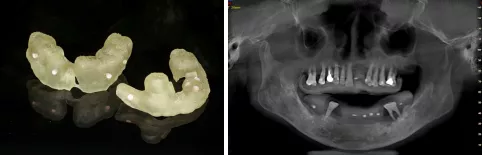

- 依据患者CBCT和口内模型,制作放射导板,患者戴入放射导板,拍摄CBCT,

- 通过士卓曼CoDiagnostix导板软件将口腔软、硬组织数据进行拟合,使用导板软件内的模拟拔牙功能,设计360数字化种植导板并打印成型。

- 使用全可调式𬌗架进行数据位点转移,术后制作临时修复义齿

- 第三:本病历余留牙均松动三度,无法作为配准参考标志,我们借助个性化放射导板的方式完成CBCT与软组织信息与排牙信息的融合,并据此最终生成精准高的360数字化导板及即刻修复的临时义齿。